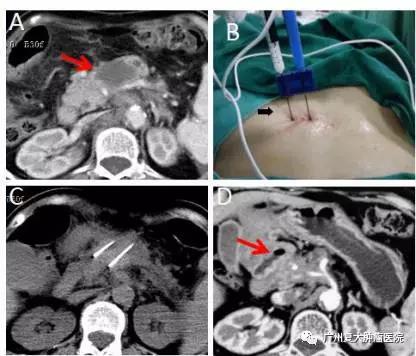

胰頭頸部腫瘤納米刀消融